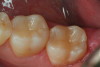

Fig 7. An occlusal view of the completed composite restoration of tooth No. 13.

Figure 7